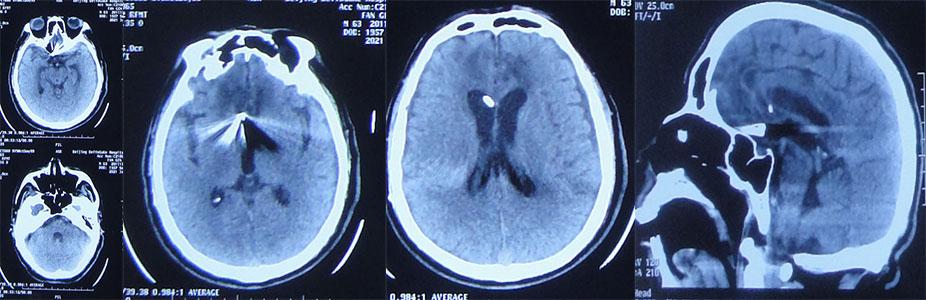

入院第一天(2020年10月17日)23时50分,急诊行动脉瘤栓塞术+右侧脑室外引流术。入院第二天(2021年10月18日),复查头部CT示动脉瘤栓塞+脑室外引流术后,脑室内血肿铸型( 图-3 )。

图-3: 2020年10月18日头部CT